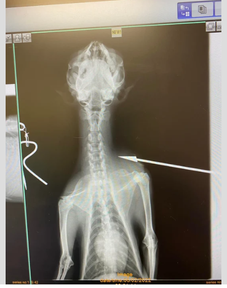

After taking X-rays, veterinarians learned that Nakoa had been shot twice. PAWS of Hawaii said: “To make it worse, this was NOT a BB gun, but real bullets. Someone shot this innocent animal and left him to die on the side of the road.”

KITV reports that Ku'ulei Durand, Executive Director of PAWS of Hawaii, explained: “It fully severed his spine, just shattering the vertebrae. They said if the bullet had missed his spine, we would've been able to save him. But, because it severed his spine he has severe damage to all of his body, and he's going to be a paraplegic dog for the rest of his life.”

Durand also explained that the bullets vets extracted from Nakoa’s body will be sent “over to authorities to try and figure out who did this to this dog.” PAWS of Hawaii said Nakoa was shot with a 9mm.

Furthermore, vets performed a CT scan and as Durand explained: “It's actually very important to do his CT scan because not only will this tell us what's wrong with him, the CT scan would be able to be used in prosecuting whoever it is that did this to him.”